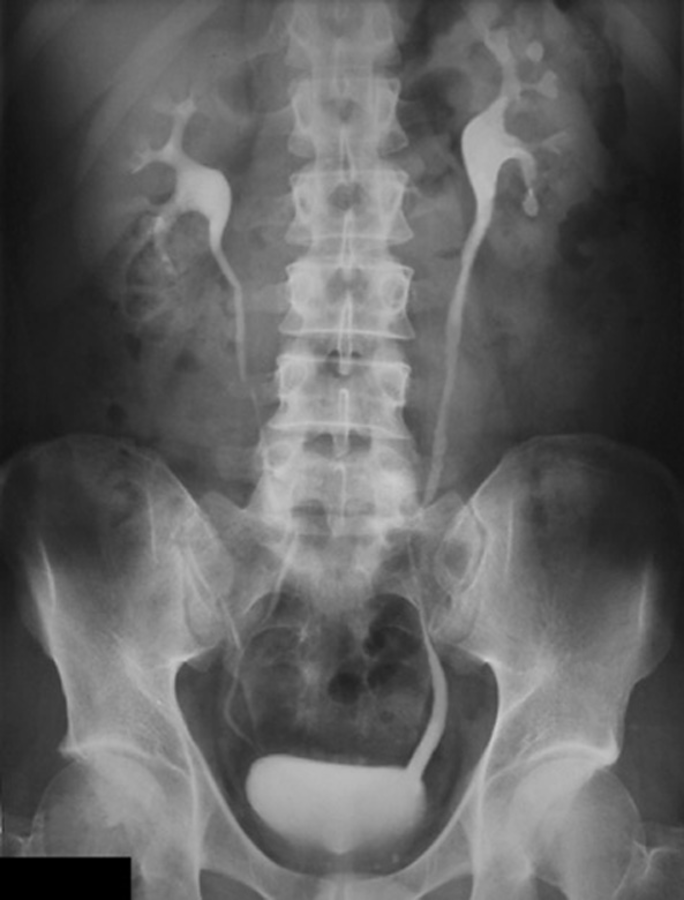

Der erste Fall einer kontrastmittelinduzierten Nierenschädigung wurde nach einer Urographie beschrieben. Der erste Fall einer kontrastmittelinduzierten Nierenschädigung wurde nach einer Urographie beschrieben. © iStock/luismmolina; wikimedia/Glitzy queen00

Der erste Fall einer kontrastmittelinduzierten Nierenschädigung wurde nach einer Urographie beschrieben. Der erste Fall einer kontrastmittelinduzierten Nierenschädigung wurde nach einer Urographie beschrieben. © wikimedia/Glitzy queen00